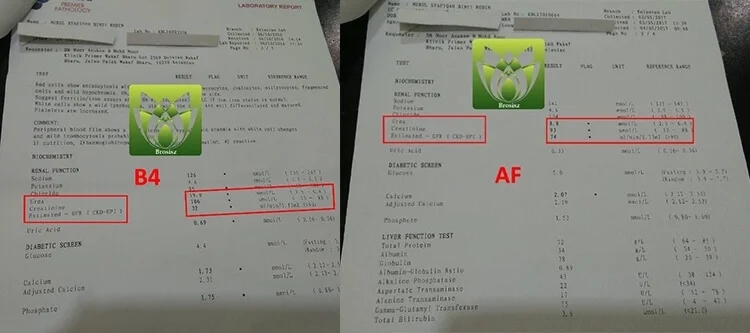

看看這個報告有很大的改善:

B4 AF 标准指数

Urea 19 8.8 ( 2.5 – 6.4 )

Creatinine 186 93 ( 53 – 88 )

CKD-EPI 32 74 ( >90 )

Urid Asid 0.69 0.33 ( 0.16 – 0.36 )

【 醫生嚴重警告他腎臟指數不樂觀 】- 服用後有很大的改善!他說非常有效!

這位是SetapakKL。美國雲杉腎寶片就是他的好朋友推薦他服用的,情況是這樣的:他長期尿酸,痛風,尿液渾濁,尿泡,糖尿病打胰島素,血壓偏高,就在近期體檢報告醫生嚴重警告他腎臟指數不樂觀,飲食一定要注意,阿民就問到有方法解決嗎,他不想要洗腎,醫生跟他說這樣子是可能可以拉長腎臟的壽命,西醫方面洗腎是唯一的結果【因為他健康問題太多了】。但是他經濟能力有限,也不想沒嘗試就放棄,洗腎的話,每個月的開銷他會更辛苦,最後在網路上購買了【美國雲杉腎寶片】,沒想到服用3個月後,尿酸,痛風,尿液渾濁通過好了,血壓也正常了,腎臟指數也樂觀了!